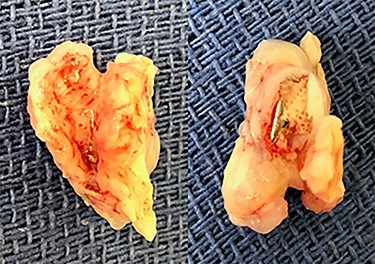

Eight months after MitraClip implantation, the patient underwent MV replacement via a minimally invasive right thoracotomy. The patient underwent cardiopulmonary bypass via the femoral vessels. Through a right thoracotomy, a left atriotomy was made. The previously placed mitral clips were associated with fibrotic changes and damage to the leaflets (Figs 2 and 3). The left ventricle was noted to be severely dilated. The MV was replaced with a 25-mm bovine pericardial bioprosthesis. Cardiopulmonary bypass was terminated at the conclusion of the operation with moderate inotropic support and satisfactory hemodynamic parameters. The intraoperative transesophageal echocardiogram showed mild improvement of LVEF from 20 to 30%. The bioprosthetic mitral valve was functioning appropriately without para-valvular leak and a transvalvular gradient of <2 mmHg. Postoperative transthoracic echocardiogram revealed an LVEF 30–35% and a normally functioning bioprosthetic MV with a mean transmitral gradient of 5 mmHg. The patient was extubated, weaned off inotropic support, and transferred out of the intensive care unit on post-operative days two, four and seven, respectively. She was ultimately discharged to home with home services. Her echocardiogram remained stable at time of discharge and 1 month follow-up. At 6 months postoperatively, the patient continued to progress with one brief hospital admission for non–cardiac-related concern.

(A) Echocardiogram showing mitral clip (white arrow) at 4 months after clip placement; (B) at 7 months, left ventricular ejection fraction was 15–20%, diastolic and systolic diameters were 54 and 51 mm, respectively, and mean transmitral gradient 2.1 mmHg.